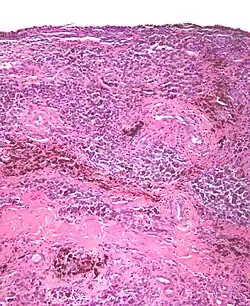

| Micrograph of diffuse TGCT, also known as pigmented villonodular synovitis. H&E stain. | |

Tenosynovial giant cell tumor (TGCT) is a non-malignant tumor defined histologically as inclusions of “osteoclast-like” multinucleated giant cells, hemosiderin, and macrophages.[1] This histology can present one of 2 clinically distinct ways. Localized/nodular TGCT (L-TGCT), sometimes referred to as “giant cell tumor of the tendon sheath”;[2]: 100 is a common tumor that presents as a slow-growing, encapsulated, localized and limited bump, most frequently in the fingers. [3] Diffuse TGCT (D-TGCT) — also called pigmented villonodular synovitis (PVNS)— is a rare tumor that presents as a proliferative, destructive, intra-articular lesion, most commonly in the knee.[2]: 102 [4] D-TGCT tumors often develop from the lining of joints (also known as synovial tissue).[5][2][2]: 100 [6][6]: 245 . Common symptoms of D-TGCT include swelling, pain, stiffness and reduced mobility in the affected joint or limb.[2]: 102